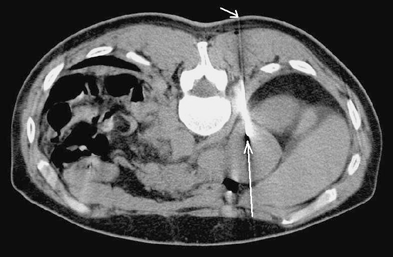

Значительно улучшает качество диагностики опухолей надпочечников использование КТ. Минимальная величина опухоли, определяемая этим методом, составляет от 0,5 до 1 см (Бондаренко В.О., 1986). КТ позволяет определить топографию надпочечников, форму, величину, структуру. Точность КТ в диагностике опухолей надпочечников в настоящее время составляет 80–95,7% (Авдеева Т.Ф. и др., 1992) (рис. 2).

Рисунок 2. КТ — опухоль (аденома) левого надпочечника